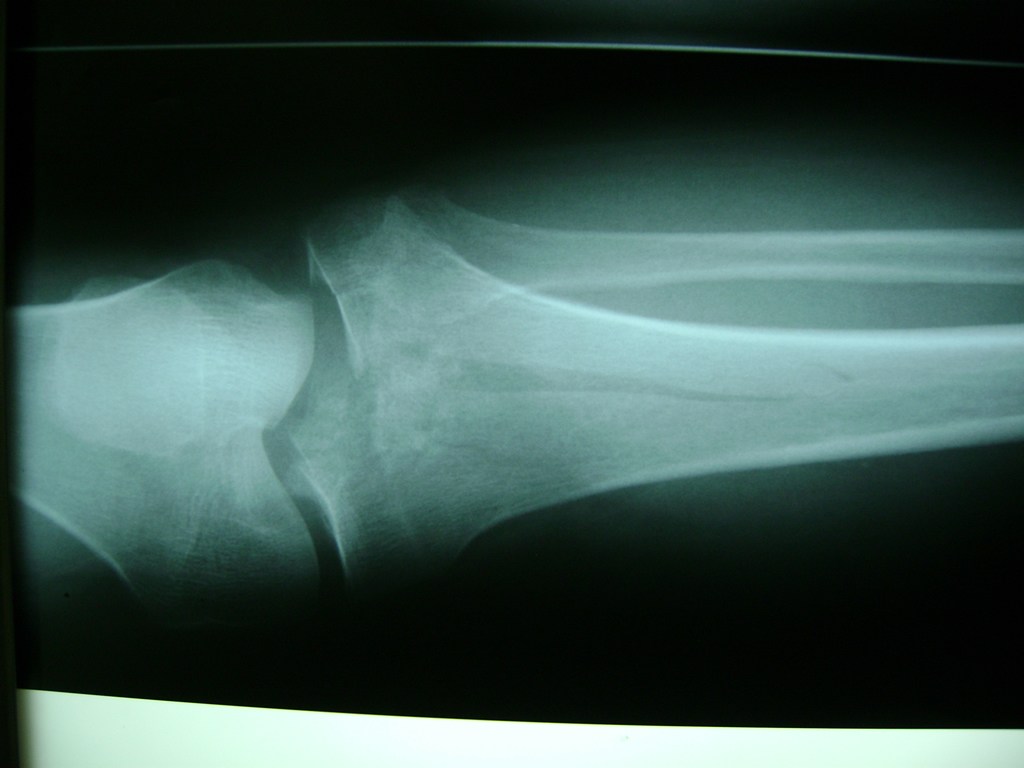

Cirugías de Peroné y Tibia

La artroscopia de rodilla es un cirugía en el cual la estructura interna de la articulación es examinada ya sea para realizar un diagnostico o para realizar un tratamiento, este procedimiento se realiza utilizando un instrumento parecido a un pequeño tubo llamado artroscopio.